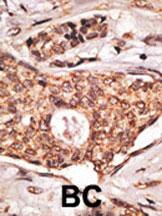

- Formalin-fixed and paraffin-embedded human lymph with ICOS Antibody (C-term), which was peroxidase-conjugated to the secondary antibody, followed by DAB staining. This data demonstrates the use of this antibody for immunohistochemistry; clinical relevance has not been evaluated.